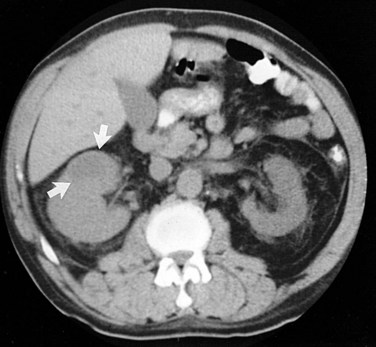

These studies are commonly used to evaluate patients initially for complicated UTIs or factors or to reevaluate patients who do not respond after 72 hours of therapy (see later). Ultrasonography (Fig. 10–19) and CT show renal enlargement, hypoechoic or attenuated parenchyma, and a compressed collecting system. They also may delineate focal bacterial nephritis and obstruction. When parenchymal destruction becomes pronounced, a more disorganized parenchyma and abscess formation associated with complicated renal and perirenal infections may be identified (Soulen et al, 1989).

Figure 10–19 Acute pyelonephritis. Ultrasound image of the right kidney demonstrates renal enlargement, hypoechoic parenchyma, and compressed central collecting complex (arrows).

(From Schaeffer AJ. Urinary tract infections. In: Gillenwater JY et al, editors. Adult and pediatric urology. Philadelphia: Lippincott William & Wilkins; 2002. p. 211–72.)